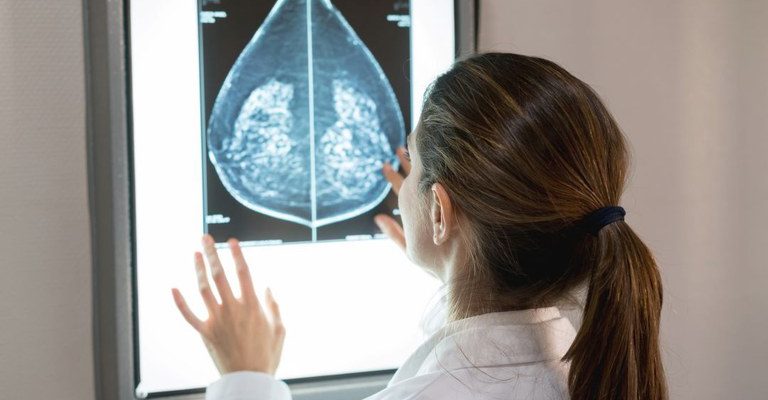

Governo do Brasil vai garantir o acesso à mamografia no Sistema Único de Saúde (SUS) a mulheres de 40 a 49 anos, mesmo que elas não apresentem sinais ou sintomas de câncer.

Essa faixa etária concentra 23% dos casos da doença e a detecção precoce aumenta as chances de cura. A medida integra um conjunto de ações anunciadas nesta terça-feira, 23 de setembro, pelo ministro Alexandre Padilha (Saúde).

Os anúncios são voltados à melhoria do diagnóstico e assistência, com início do atendimento móvel em 22 estados pelo programa Agora Tem Especialistas e a oferta de medicamentos mais modernos. A

recomendação para as mulheres a partir dos 40 anos é que o exame seja feito sob demanda, em decisão com o profissional de saúde. A paciente deve ser orientada sobre os benefícios e desvantagens de fazer o rastreamento.

Mulheres nesta idade tinham dificuldade com o exame na rede pública de saúde em função da avaliação de histórico familiar ou necessidade de já apresentar sintomas. Apesar disso, as mamografias no SUS em pacientes com menos de 50 anos representam 30% do total, equivalente a mais de 1 milhão em 2024.

“Garantir a mamografia a partir dos 40 anos no SUS é uma decisão histórica. Estamos ampliando o acesso ao diagnóstico precoce em uma faixa etária que concentra quase um quarto dos casos de câncer de mama”, afirmou o ministro Alexandre Padilha.

Outra medida é a ampliação da faixa etária para rastreamento ativo, quando a mamografia deve ser solicitada de forma preventiva a cada dois anos. A idade limite, que até então era de 69 anos, passará a ser de até 74 anos. Quase 60% dos casos da doença estão concentrados dos 50 aos 74 anos e o envelhecimento é um fator de risco.